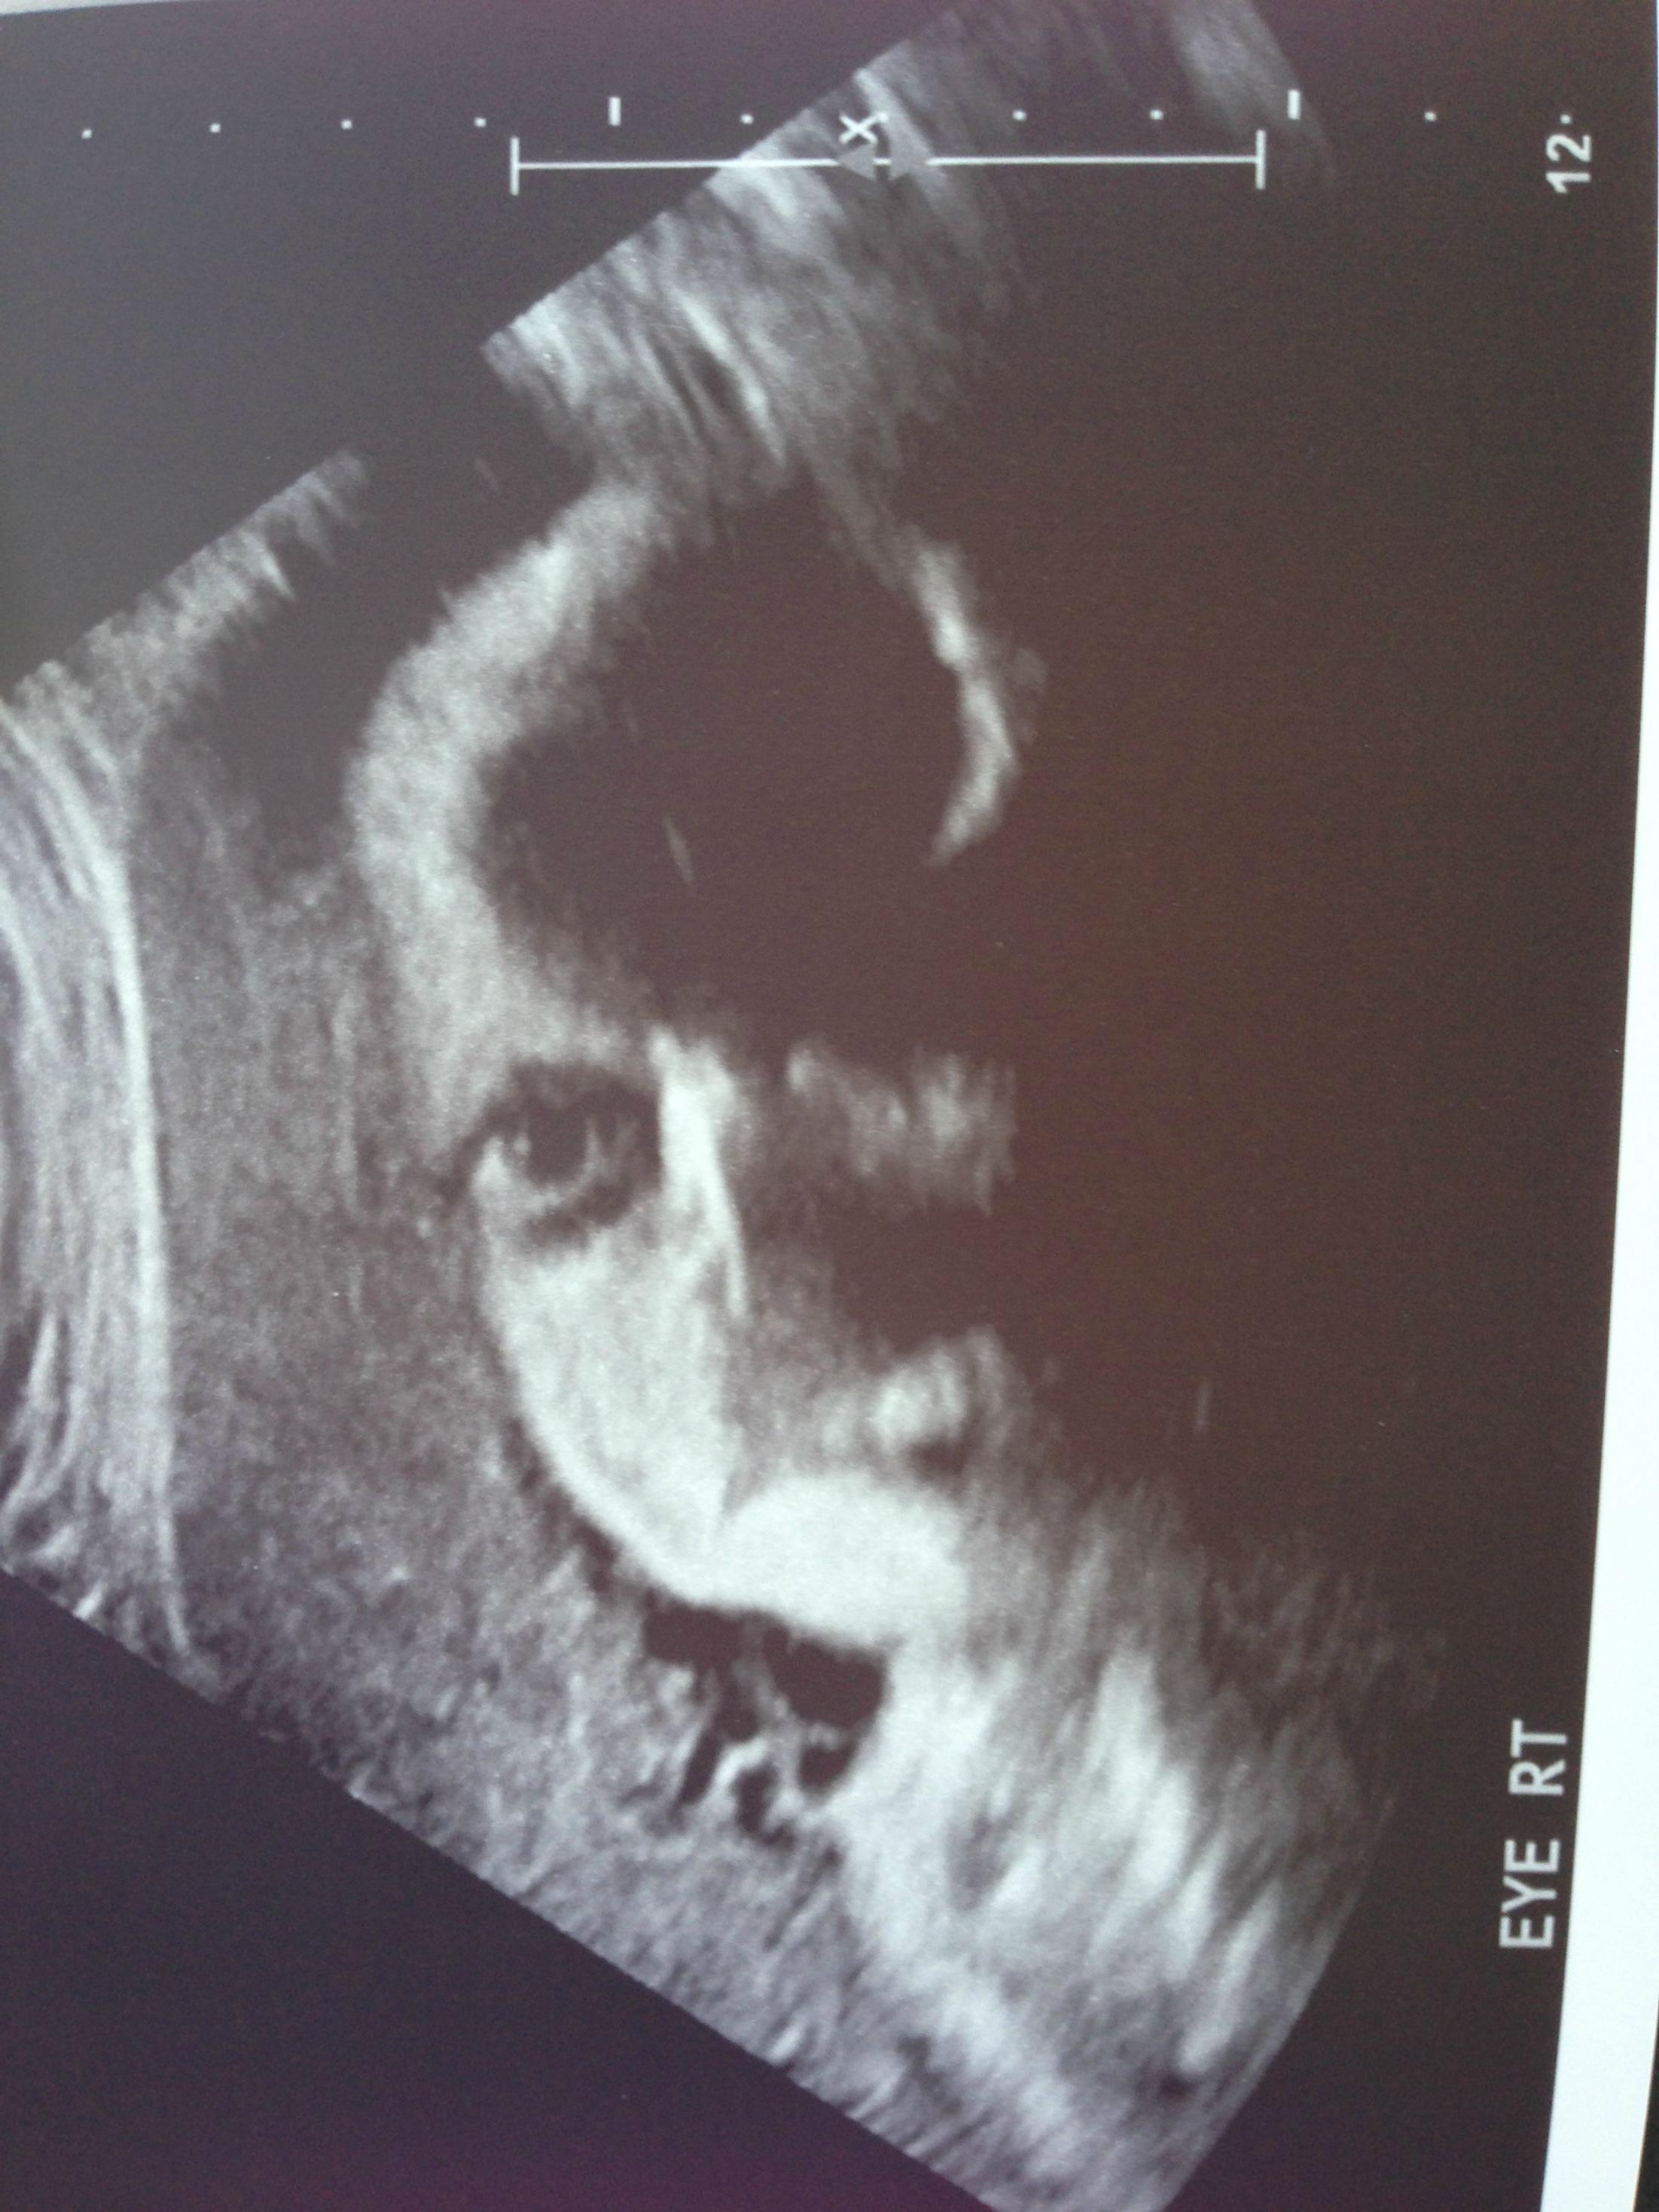

Что за пихдец на пике? Этому мертвому эмбриону менее 5ти месяцев, зачем эта поехавшая сука устроила цирк. Сукпздц.

>>55798658

он же мёртвый, нахуя ему шапочка?

Угадай, чья психика сломана в раннем детстве пизданутой, религиозной мамашей?